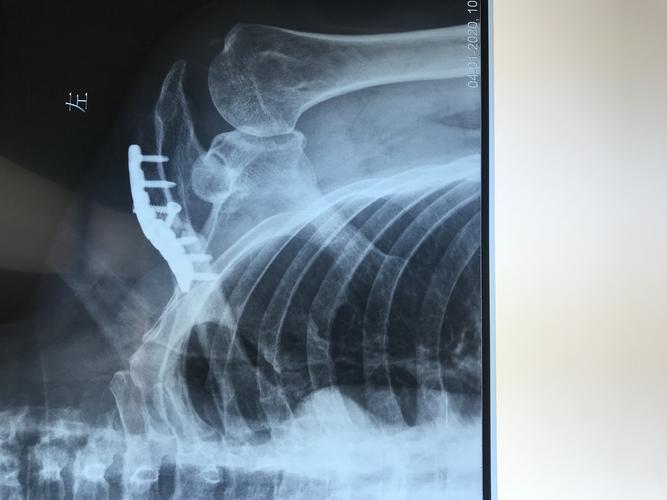

锁骨炎的症状图片

锁骨炎的症状图片,舌头炎的症状图片

锁骨骨折的微创治疗

锁骨骨髓炎,外架